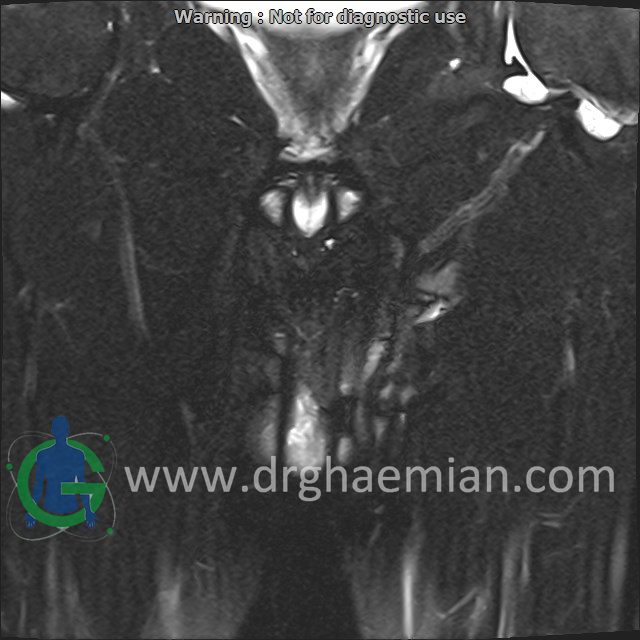

MRI OF SCROTUM

(with & without contrast)

Technique : Axial and coronal T2 , coronal T1

:REPORT

a well – defined solid cystic mass lesion ( 22x35mm ) in right testis , with DWI restriction , with cystic degeneration – necrosis , with suggestive sign of capsular invasion in anteroinferior of right testis & with post contrast mild enhancement suggestive for

1.non seminoma

2.cord abscess with post medical treatment changes

are seen